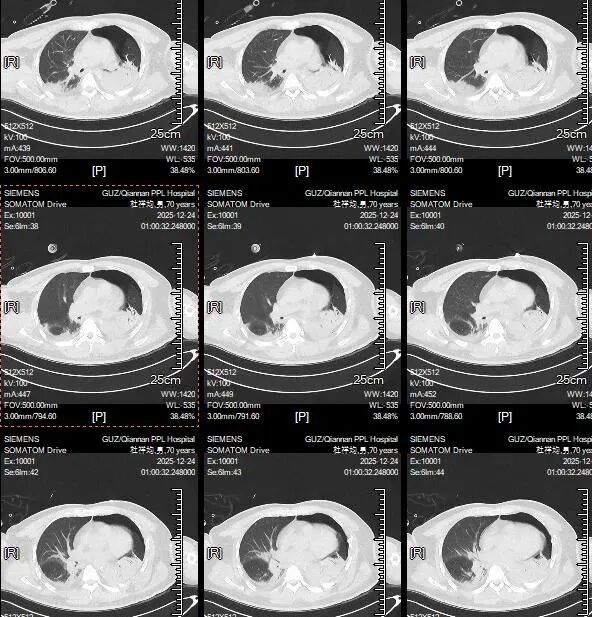

入院时胸部CT平扫 :双肺挫伤,双侧血气胸